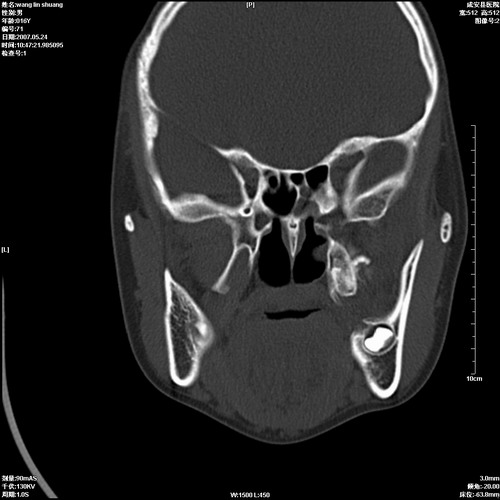

病人,男 16岁,鼻旁右肿胀,其余无不适感,ct图片

1、典型右侧根尖囊肿。

2、双侧上颌窦、筛窦、蝶窦炎

右侧上颌骨含牙囊肿.双侧上颌窦炎症.

右侧上颌骨含牙囊肿.双侧上颌窦、蝶窦右侧炎症.

1、左侧上颌骨含牙囊肿。